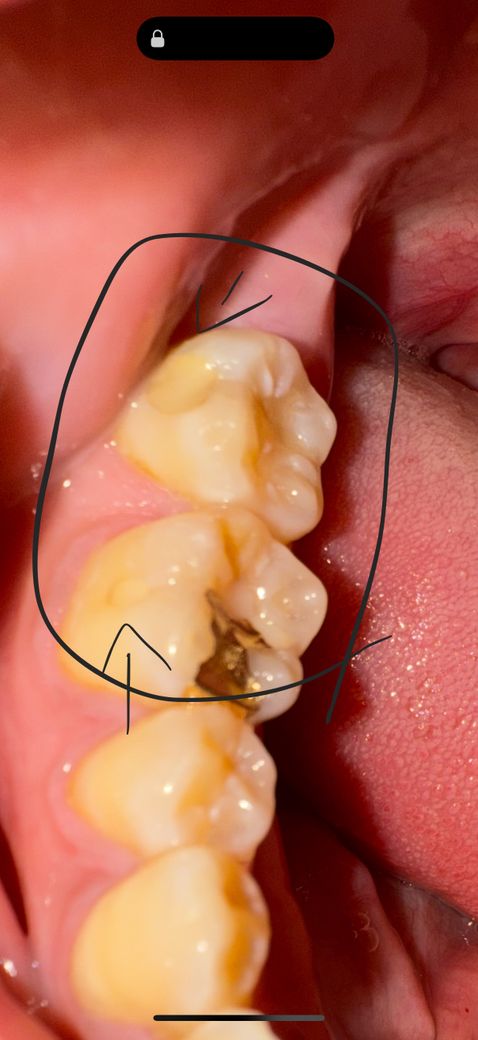

치과를 자주다녀서 충치인지 모르겠어요 자국만 봐서는 두개다 비슷한 누런색이고 부드럽게 조금 파인 느낌인데 충치인지 알수있을까요

충치는 아니며 이전에 레진 계통으로 충치치료한 자국이거나, 아니면 그부위만 치아 칼라가 조금 다르게 보이는 것일 수도 있습니다.

치료를 했던 레진에 착색이 된 것으로 판단됩니다. 충치가 진행된 것 같지는 않은 것 같습니다.

저부위는 충치는 아니고 예쩐에 치료한곳이 시간이 지나면서 주변부위로 약간 착색이 생겻다고 생각하시면될것같습니다.

네 떼운흔적입니다 buccal fit부위를 레진등의 재료로 떼운 것 같습니다 경계면에 틈이 생겼가면 치과가서 다시 하는게 좋습니다